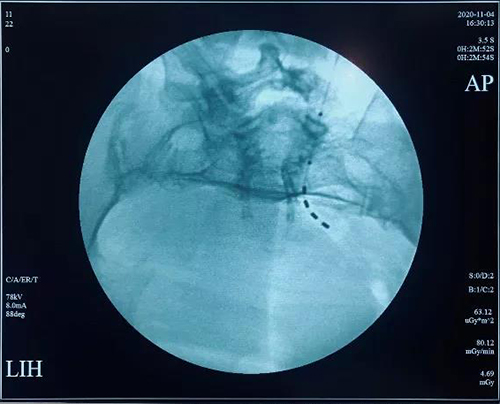

省立医院神经源性膀胱诊疗MDT还与北京医院泌尿外科、北京博爱医院泌尿外科山东大学第二医学尿动力学研究室建立广泛深入的合作关系。启动会还邀请北京医院著名尿控专家张耀光教授进行了神经源性膀胱患者骶神经调控的手术演示以及专题讲座。山东大学第二医院的张秀琳教授就神经源性膀胱的尿流动力学的表现做出了解析。